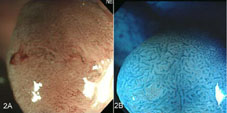

接著同時使用狹帶域光觀察及放大內視鏡(圖2A),發現息肉表面微血管為網狀分佈,粗細度不一,根據「佐野分類法」為第IIIA型表面微血管(CP type IIIA),判斷可能為高度分化不良的腺瘤或早期黏膜內癌,勢必需要切除,否則會逐漸演變成進行性大腸癌。以indigo carmine色素染色再配合放大內視鏡(圖2B)觀察表面紋路,其樹枝狀紋路判讀為「工藤第四型」(Kudo’s type IV),但尚未出現最危險的「工藤第五型」紋路(Kudo’s type VN,代表腫瘤已侵蝕深部),因此判斷可以用大腸鏡黏膜切除術(EMR,也可稱為息肉切除術,endoscopic polypectomy)把腫瘤完全切除。